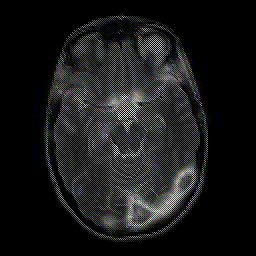

overlay -- Slice #10

[Home][Help][Clinical] Slice 10